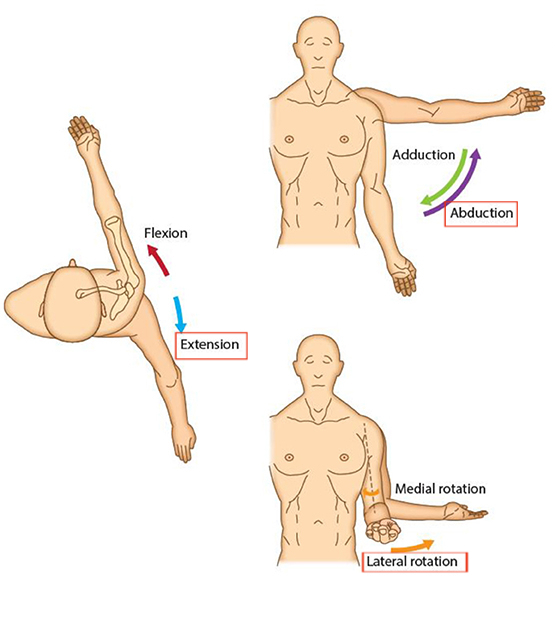

견갑골의 움직임은 3가지 움직임(Motion)과 2가지 미끄러짐(translations)으로 나눌 수 있습니다.

움직임(motion) - 한 축을 중심으로

ㆍ회전외회전(ER) / 내회전(IR)

ㆍ앞쪽 기울어짐(Anterior tilting) / 뒤쪽 기울어짐(Posterior tilting)

ㆍ상방회전(Upward rotation) / 하방회전(Downward rotation)

2. 미끄러짐(Translation) - 특정 평면을 따라 미끄러짐 운동

거상(Elevation) / 하강(Depression) = Upward/downward sliding on the thorax

내전(후인, Adduction) / 외전(전인, Abduction) = Medial/lateral sliding around the curvature of the thorax